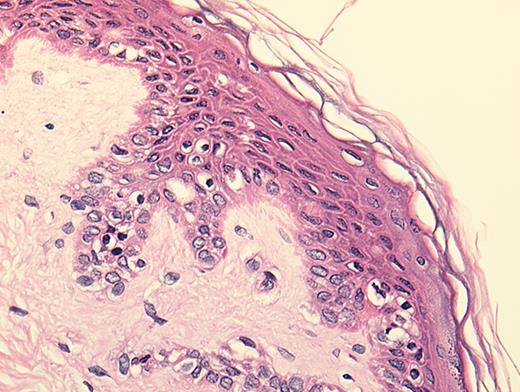

(in Barrett et al). In situ localization of mHa-specific cytotoxic T lymphocytes (CTLs) in the skin explant assay.

Skin sections of an HLAA2 male individual were incubated with autologous peripheral blood mononuclear cells (PBMCs)—data not shown, or with H-Y- or HA-1-specific CTLs.

Figure 2a. H-Y-specific CTLs showing grade IV reactions.

Figure 2b. Skin sections incubated with FITC-conjugated CD8 antibodies (green) plus APC-conjugated (red) tetrameric HLA-A2-H-Y peptide complex (H-YA2 tetramer)—analyzed by confocal microscopy

Figure 2c. Mild histopathological changes induced by HA-1-specific CTLs.

Reprinted with permission of the Nature Publishing Group (http://www.nature.com).44